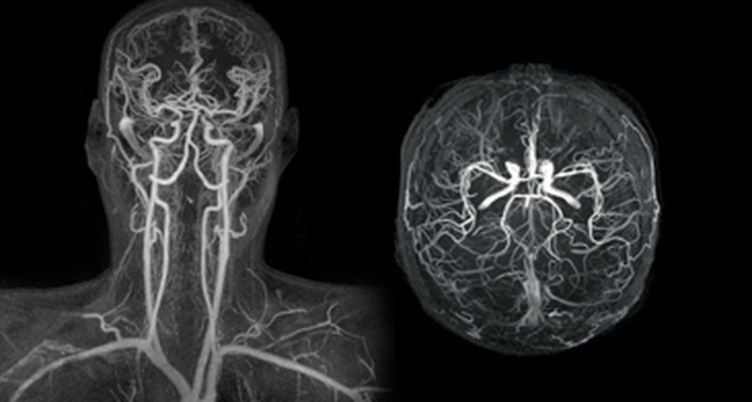

Διαγνωστικές εξετάσεις αρτηριών

Οι διαγνωστικές εξετάσεις των αρτηριών περιλαμβάνουν διάφορες μεθόδους που χρησιμοποιούνται για να αξιολογήσουν την κατάσταση και τη λειτουργία των αρτηριών.

Η Μαγνητική Αγγειογραφία (MRA) είναι μια μη επεμβατική εξέταση που χρησιμοποιεί τη μαγνητική τεχνολογία και τους υπολογιστές για να δημιουργήσει λεπτομερείς εικόνες των αγγείων στο εσωτερικό του σώματος, συμπεριλαμβανομένων των αρτηριών και των φλεβών.